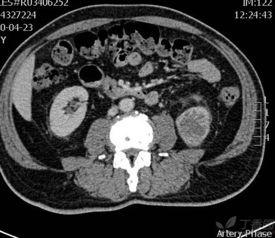

首先,得先给你科普一下什么是双肾B超。简单来说,双肾B超就是通过超声波来观察肾脏的一种检查方法。它可以帮助医生了解肾脏的大小、形态、位置以及内部结构,对于诊断肾脏疾病有着非常重要的作用。